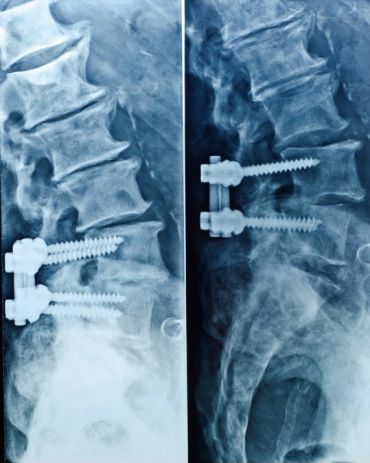

Artrodese da coluna lombar

Texto informativo sobre o procedimento de artrodese da coluna lombar.